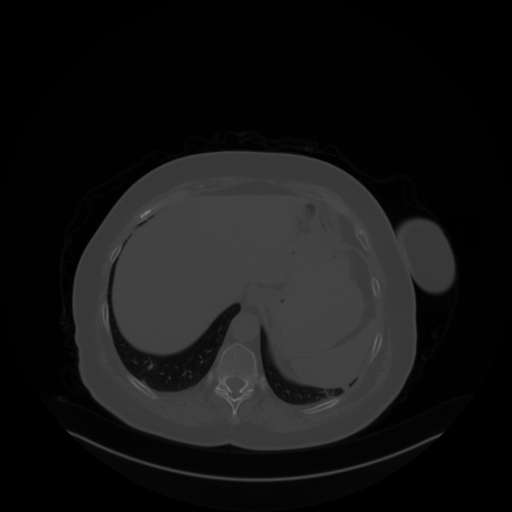

Original NATIVE CT scan (input)

Mediastinum window (WL 40, WW 400 β†’ Low βˆ’160, High +240)

Reconstructed NATIVE CT scan (cycle consistency)

Original VENOUS CT scan

Generated VENOUS CT scan (A→B translation)